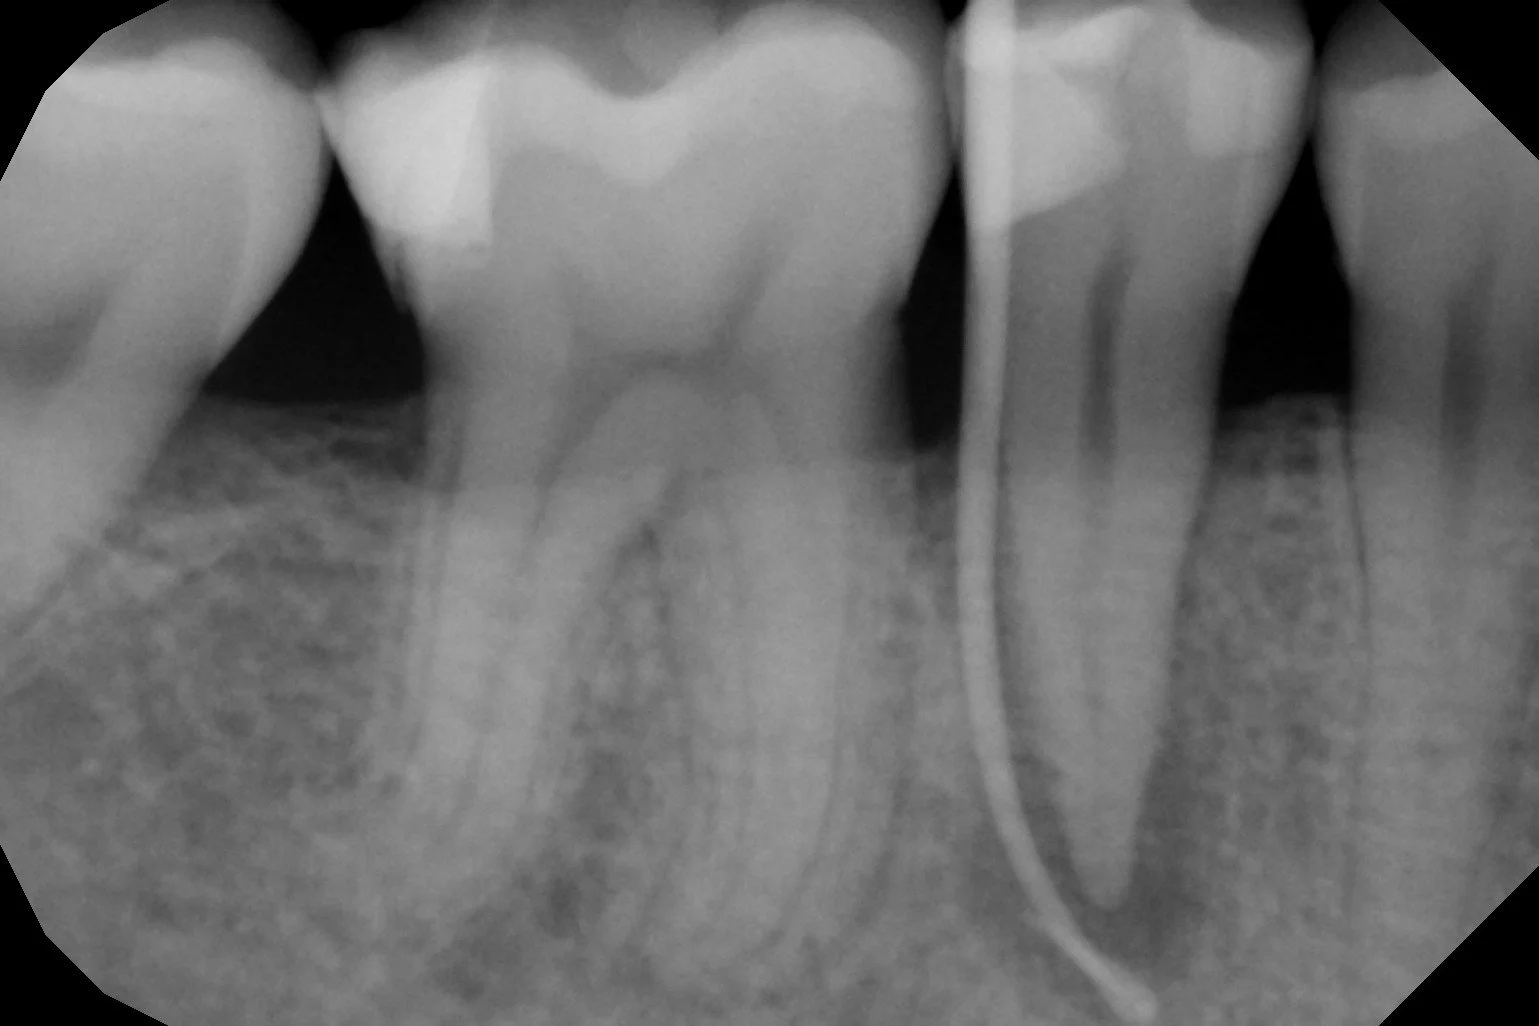

La Endodoncia consigue eliminar el nervio de los dientes con dolor por caries o algún traumatismo y rellenarlo con material biocompatible, conservando el diente sin tener que extraerlo.

En nuestra clínica se realizan endodoncias por un Especialista En Endodoncia tratando desde casos sencillos a casos complejos de retratamientos o fracasos en endodoncias antiguas.

Utilizamos técnicas avanzadas de diagnóstico en endodoncia como la Radiovisiografía Digital, el Localizador de Ápice y Técnicas Rotatorias de instrumentación de los conductos radiculares, utilizando el microscopio en los pacientes que lo requieren.